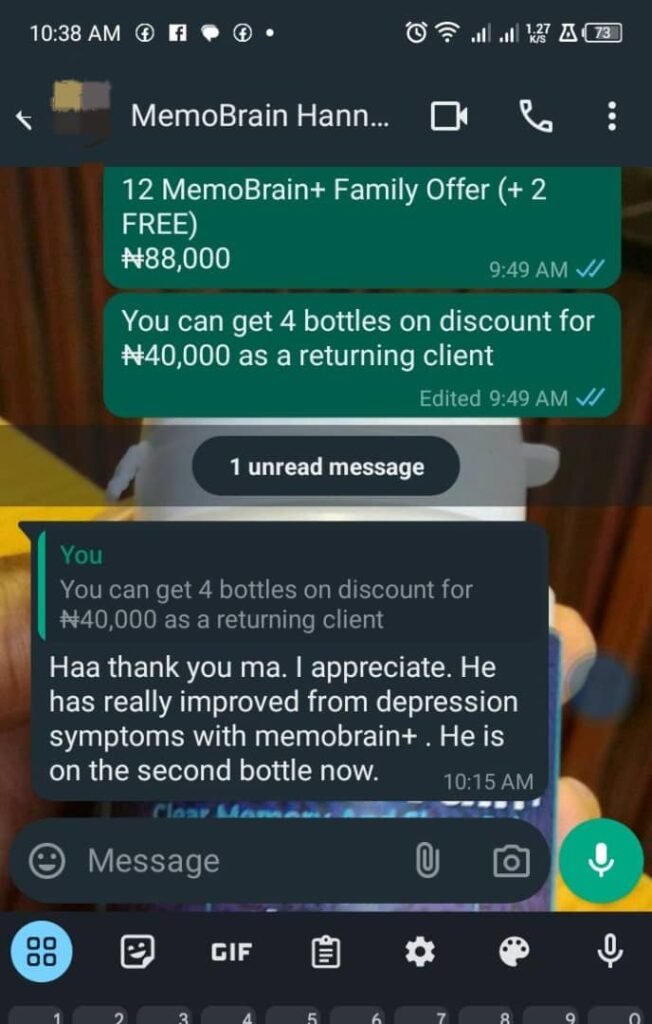

She’s not the only one

Here’s another one

And here is what Mrs Hannah has to say about MemoBrain+

Don’t take my words for it…

See what people like you are saying about MemoBrain+

"The Product is a good one"

"There are lots of improvement"